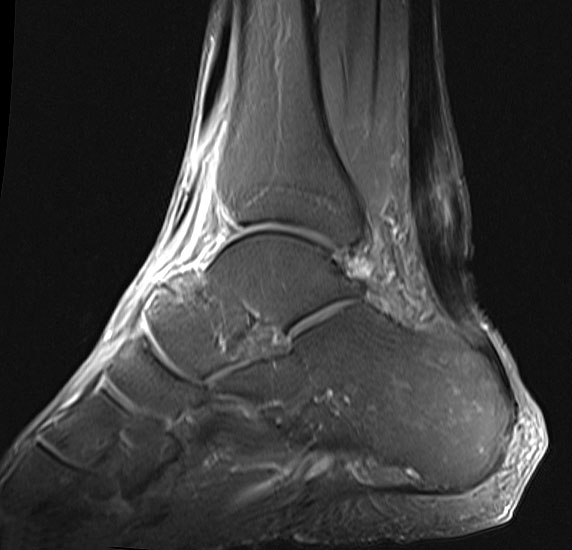

Schwere Veränderungen der Binnenstruktur der Achillessehne im MRT in den T2 gewichteten Aufnahmen als Korrelat einer ausgeprägten Achillodynie

Abbildung 7

Die Magnetresonanztomographie (MRT) hat insbesondere bei ansatznahen Beschwerden Ihren Stellenwert (Abb. 7). Sie kann ein begleitendes Knochenödem des Calcaneus wie auch ggf. eine Stressfraktur ausschließen helfen. Neben Signalalterationen insbesondere in der T2-Wichtung sind Nekrosen, Teilrupturen und begleitende Ödeme häufige Befunde, wie auch in 10% eine fettige Degeneration des M. gastrocnemius 28.